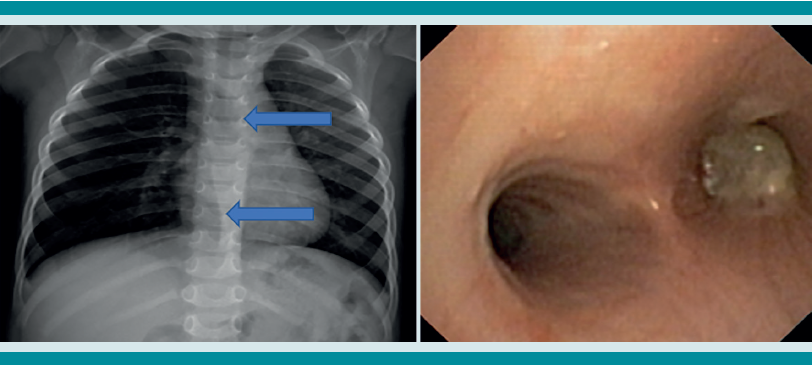

La radiografía de tórax es el primer estudio en un paciente pediátrico que llega al servicio de urgencias con sospecha de aspiración de cuerpo extraño. Gran parte de los objetos aspirados son radiolúcidos (biológicos y plásticos) y, por lo tanto, no se ven por este medio. Solo se logrará observar el cuerpo extraño en 15% de los casos (metálicos y huesos).1,6,8 Es más común identificar datos indirectos (aparecen hasta en 50% de las radiografías), que son consecuencia de la obstrucción en la vía aérea (atrapamiento de aire, atelectasias, consolidación, neumotórax) (Figuras 1,2,3,4,5). Respecto de las radiografías de tórax es que, incluso 45% pueden interpretarse normales, lo que puede resultar en un diagnóstico erróneo.1,6,9

Si al momento de consultar el paciente se encuentra en la etapa aguda, pero está estable, es decir, sin datos clínicos de inestabilidad cardiorrespiratoria, o se encuentra en la etapa oligosintomática pueden solicitarse los estudios de imagen. La radiografía de tórax es el principal recurso con el que cuentan la mayor parte de los servicios de urgencias. Es rápido, fácil, poco costoso y no requiere sedación. En caso de que sea un objeto radio-opaco, aportará el diagnóstico de manera rápida, y dará la localización del objeto (Figura 7). En caso de ser radiolúcido, la radiografía puede ser normal o mostrar los datos indirectos de obstrucción comentados. La tomografía axial computada de tórax puede considerarse si se cuenta con el recurso, tomando en cuenta lo mencionado.